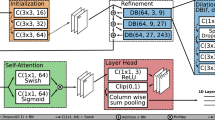

Automatic retinal layer segmentation in optical coherence tomography (OCT) images is crucial for the diagnosis of ocular diseases. Currently, automatic retinal layer segmentation works well with normal OCT images. However, pigment epithelial detachment (PED) dramatically alters the retinal structure, causing blurred boundaries and partial disappearance of the Bruch’s Membrane (BM), thus posing challenges to the segmentation. To tackle these problems, we propose a novel dual-path U-shaped network for simultaneous layer segmentation and boundary regression. This network first designs a feature interaction fusion (FIF) module to strengthen the boundary shape constraints in the layer path. To address the challenge posed by partial BM disappearance and boundary-blurring, we propose a layer boundary repair (LBR) module. This module aims to use contrastive loss to enhance the confidence of blurred boundary regions and refine the segmentation of layer boundaries through the re-prediction head. In addition, we introduce a novel bilateral threshold distance map (BTDM) designed for the boundary path. The BTDM serves to emphasize information within boundary regions. This map, combined with the updated probability map, culminates in topology-guaranteed segmentation results achieved through a topology correction (TC) module. We investigated the proposed network on two severely deformed datasets (i.e., OCTA-500 and Aier-PED) and one slightly deformed dataset (i.e., DUKE). The proposed method achieves an average Dice score of 94.26% on the OCTA-500 dataset, which was 1.5% higher than BAU-Net and outperformed other methods. In the DUKE and Aier-PED datasets, the proposed method achieved average Dice scores of 91.65% and 95.75%, respectively.